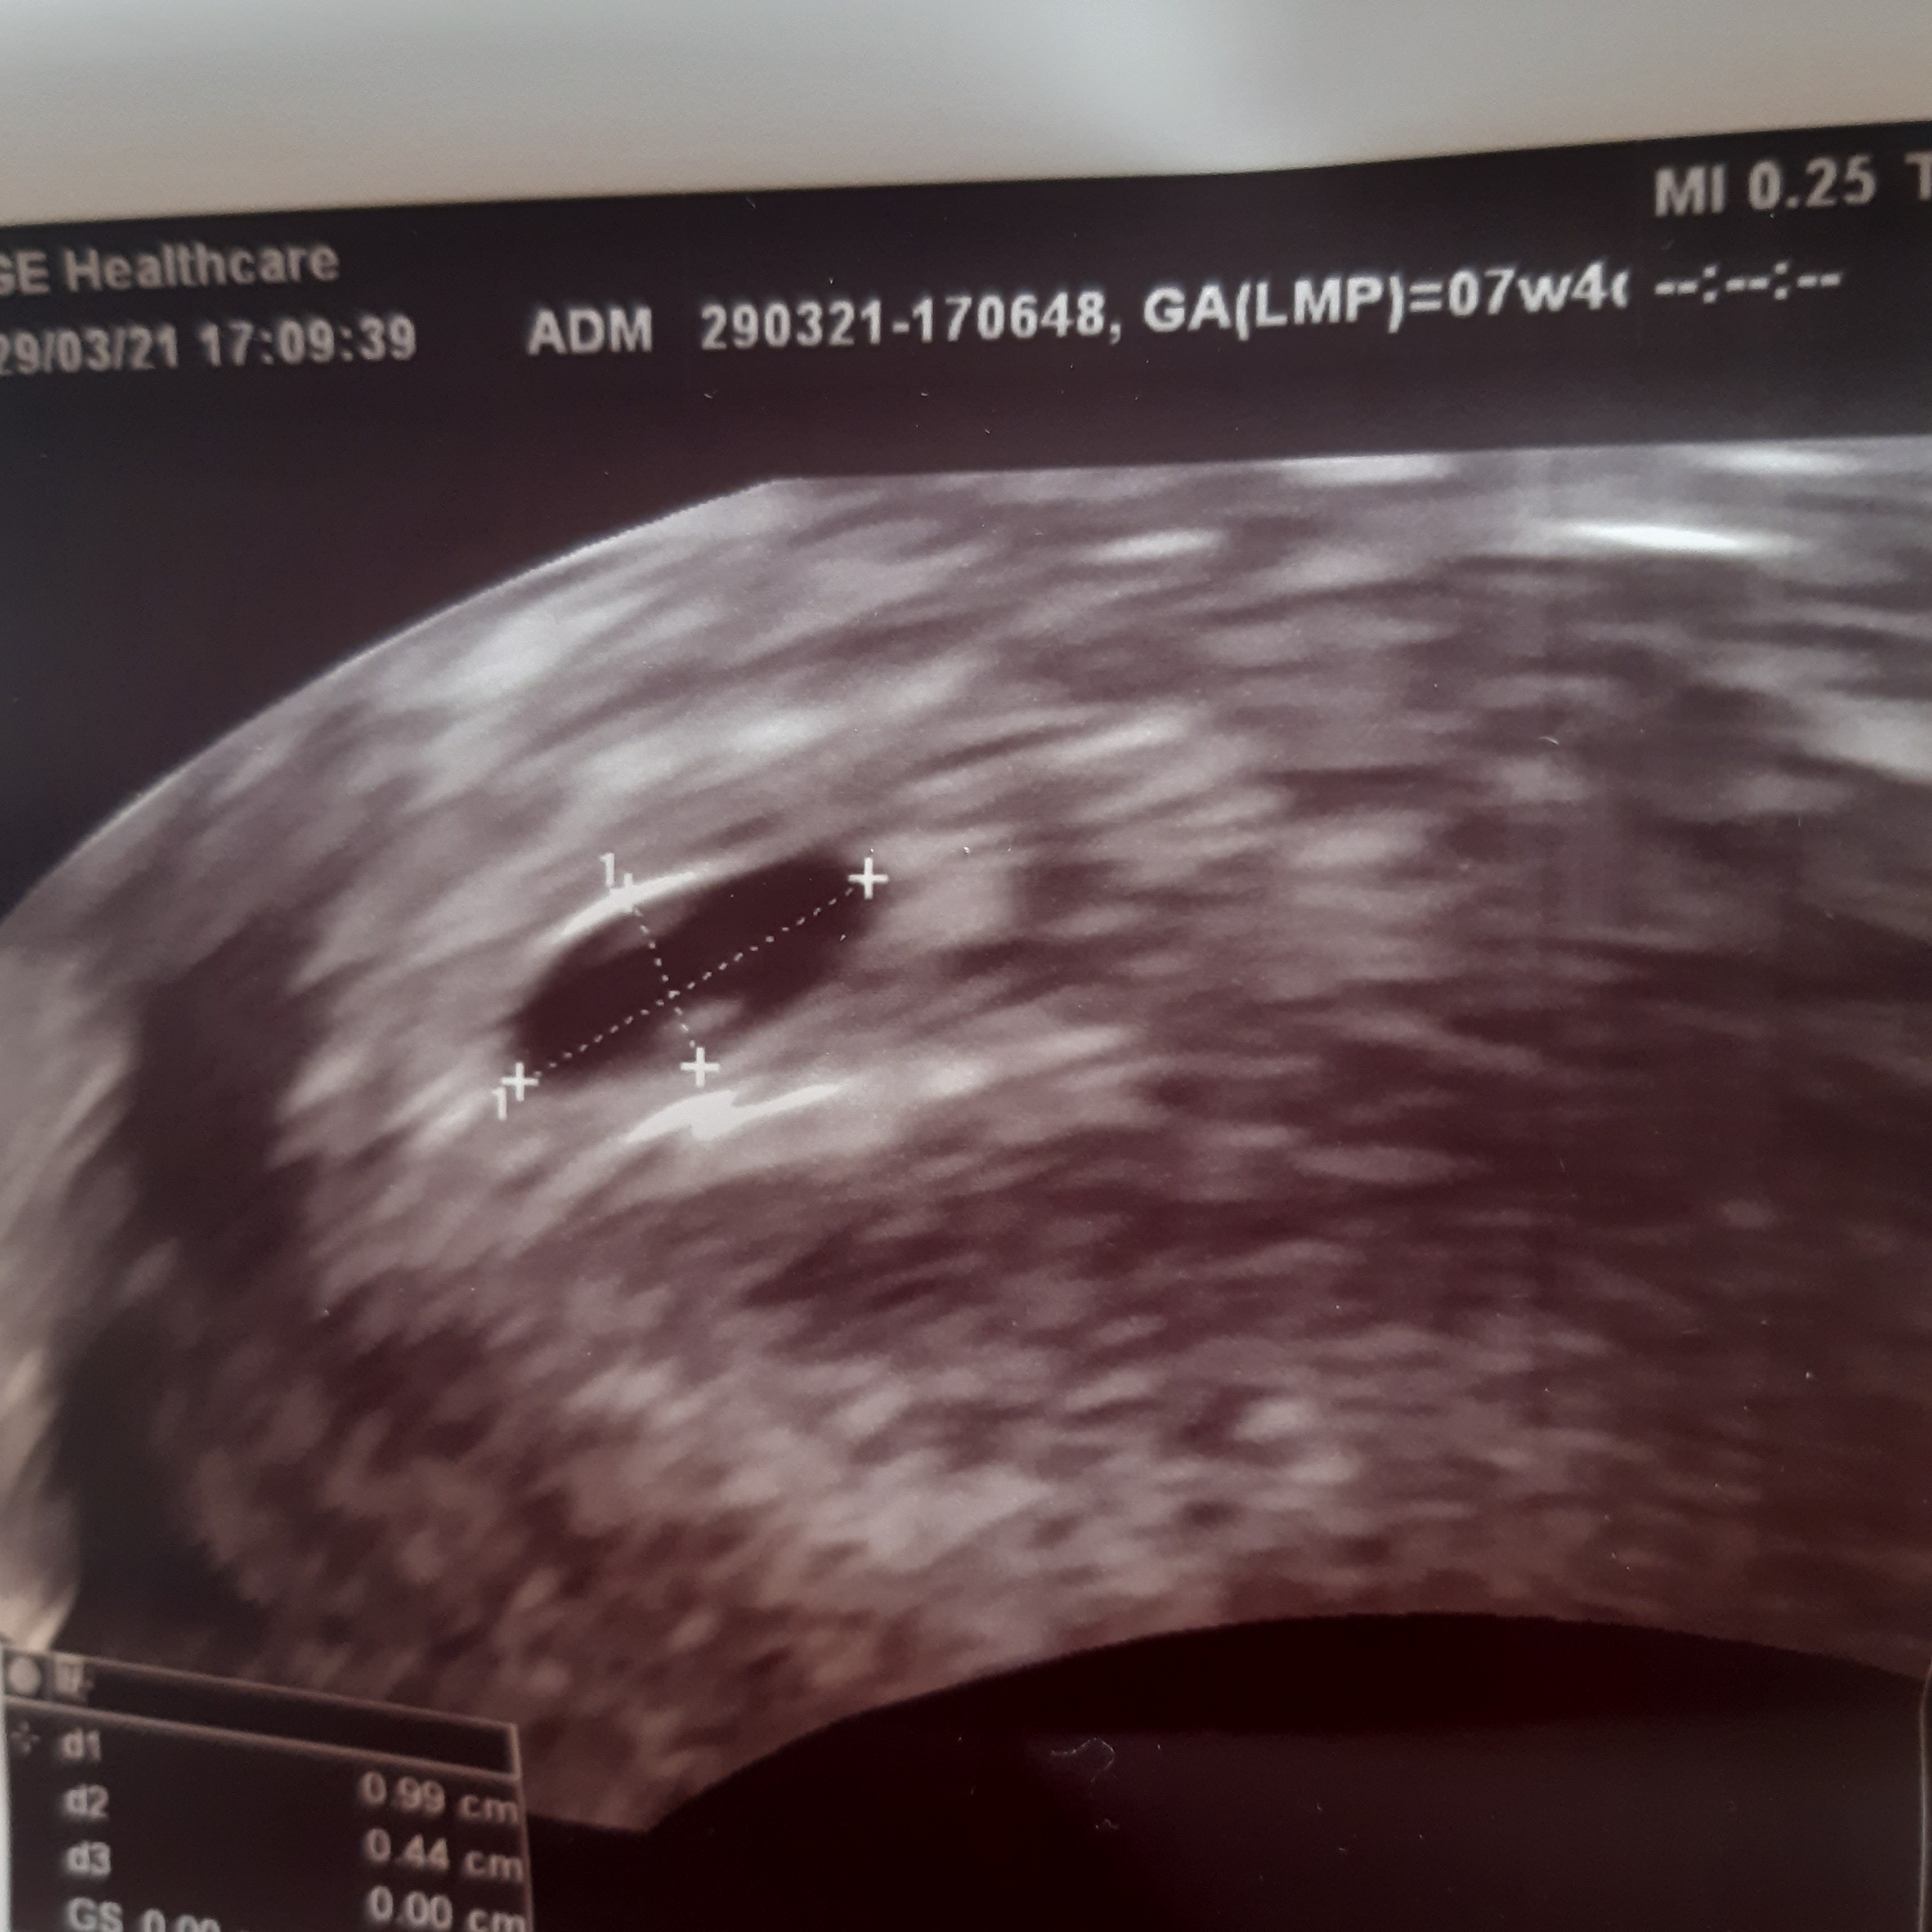

u mnie tak wygląda usg, ja ta widzę jakieś kropki ale nie znam się na tych zdjęciach, no nic trzeba czekac na kolejne usg i mieć nadzieję, że zarodek się pojawi.

• usg.jpg

usg.jpg

1,4 MB · Wyświetleń: 108